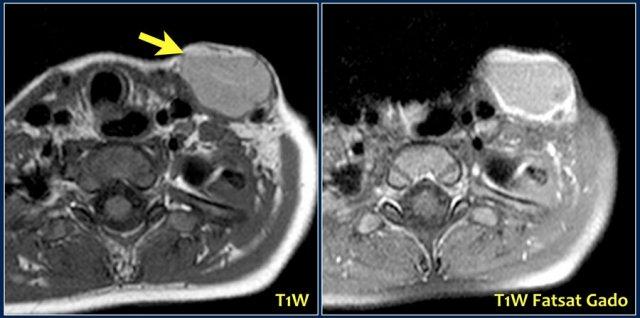

Một bé trai 3 tuổi đột ngột xuất hiện khối u vùng trên xương đòn.

Ultrasound showed a lesion with echogenic debris.

A hemorrhage in a preexisting lymphangioma was suspected.

Continue with the MRI.

Hình ảnh T1-weighted cho thấy một tổn thương tăng tín hiệu nhẹ với mức độ dịch-dịch (mũi tên).

Sau khi tiêm gadolinium, có sự tăng tín hiệu của thành nang.

The lesion subsided with conservative therapy.